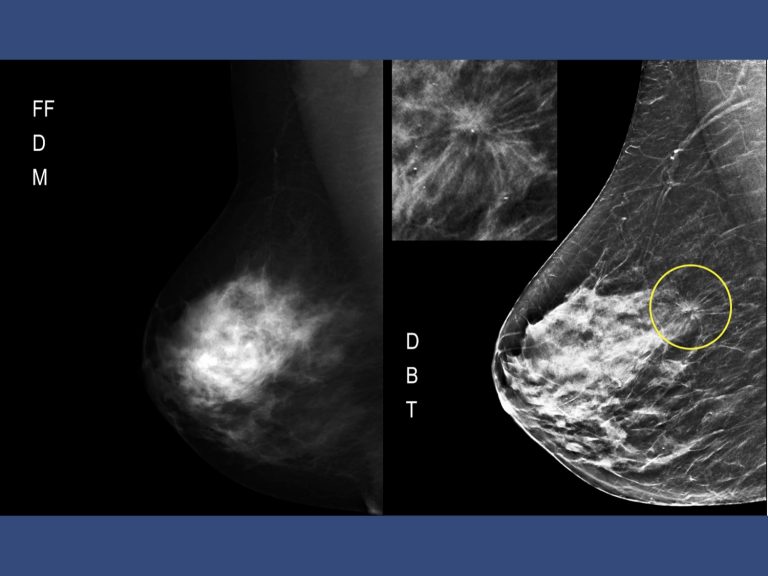

Vi sono ormai consolidate evidenze che la mammografia 3D (tomosintesi) sia più sensibile della mammografia digitale tradizionale. Non solo migliore sensibilità ma anche maggiore specificità.

La tomosintesi è tecnica più sensibile della mammografia 2D perché ottimizza i vari aspetti menzionati. L’impianto mammografico viene modificato per consentire alla sorgente radiogena di ruotare ed eseguire radiografie del seno a diversi angoli di proiezione; le immagini digitali, acquisite a bassa dose, sono poi opportunamente combinate per ricostruire le sezioni a diversa profondità. La tomosintesi in pratica è una mammografia migliore. Nata per superare i limiti della mammografia digitale 2D la tomosintesi permette di ricostruire una stratigrafia della mammella a partire da un numero finito di proiezioni bidimensionali. Di ultimissimo sviluppo è il CAD che mediante marker segnala le aree di maggiore interesse.

Ciò contribuisce a ridurre gli artefatti da sovrapposizione o sommazione e ad ovviare al mascheramento delle lesioni relativo alla densità mammaria. La tomosintesi è in grado di visualizzare separatamente oggetti posti a profondità diverse tramite l’acquisizione di molteplici proiezioni bidimensionali a bassa dose per diverse angolazioni del tubo rx intorno alla mammella con detettore fermo. I dati acquisiti vengono ricostruiti in una serie di strati sottili ad alta risoluzione.

La ricostruzione 3D supera i limiti della Mammografia 2D dovuti a densità mammaria e sovrapposizione dei tessuti che determinano mascheramento e misconoscimento dei tumori.

Analisi più accurata eliminando gli artefatti da sovrapposizione del tessuto fibroghiandolare, incrementando la risoluzione spaziale e riducendo i falsi negativi e i falsi positivi. I falsi negativi della mammografia digitale oscillano dal 10 al 30%.2. La dose di radiazione ampiamente al di sotto della dose di sicurezza, sostanzialmente analoga alla mammografia digitale ma di gran lunga inferiore rispetto alla mammografia analogica.3. La Tomosintesi c-view permette l’esecuzione della mammografia in 3D con ricostruzione mediante algoritmo matematico di una immagine 2D.